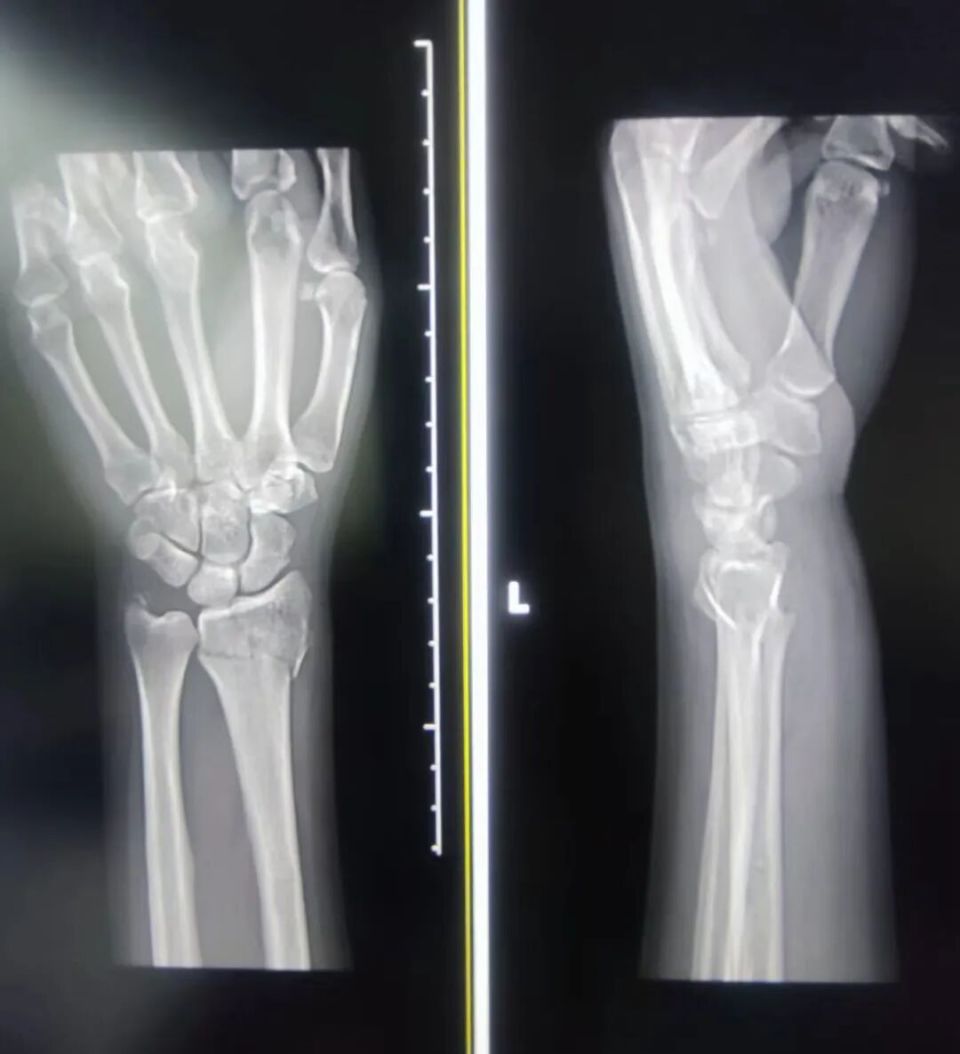

疼痛难忍的王女士紧急赶到浙江省中山医院骨伤科。接诊的蔡军辉副主任医师看到她时,她的右手手腕已经明显肿胀变形。

“这是典型的桡骨远端骨折。”蔡主任说,“今天早上我已经接诊了几个了,“前面我还接诊了一位70多岁的大伯,同样是在雪天滑倒导致手腕骨折。冬季,尤其是雨雪天气,是腕部、髋部、脊柱椎体、踝部等部位骨折的高发期。”

蔡军辉介绍,桡骨远端骨折是雪天最常见的损伤。当人体失去平衡摔倒时,潜意识会让人伸手去“刹车”,巨大的冲击力瞬间传导至手腕,脆弱的桡骨远端便成了“牺牲品”。

“好在王女士的情况属于闭合性骨折,没有伤及神经和血管。”蔡主任随即为其进行了手法复位,随着一声轻响,错位的骨头归了位,随后打上了石膏固定,“大部分这种骨折通过保守治疗都能恢复得很好,但如果移位严重,那就得进手术室了。”